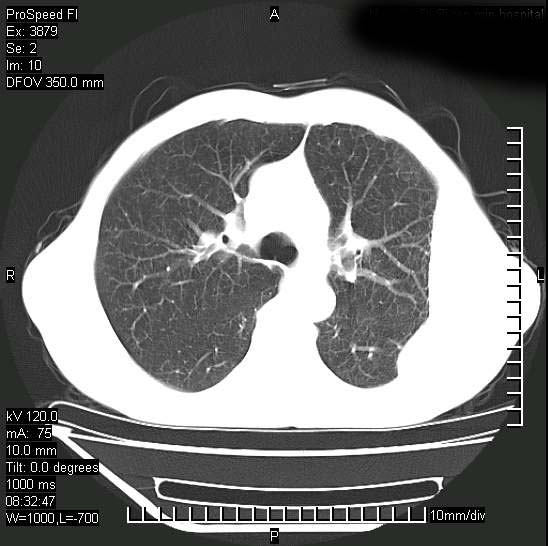

以下是引用37度在2008-6-6 11:20:00的发言:[br]1.包裹性积液,多考虑结核性;[br]2.穿刺术后改变。

以下是引用312nanyang在2008-6-6 15:12:00的发言:[br]基本支持楼主意见[br]疑问?左下肺支气管旁的软组织(16层)密度怎么解释?淋巴结还是斜裂胸膜增厚所致?能否增强进一步检查